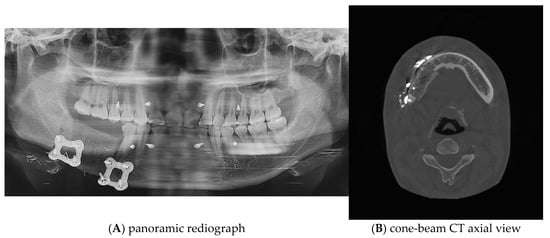

Postoperative panoramic radiographs and CBCT imaging were obtained to evaluate the error compared to the preoperative plan. (Figure 11) The evaluation was performed using Materialize 3-matic software. After aligning the preoperative plan STL model and the postoperative STL model, the average value was obtained through analysis of the difference between the two models. the average discrepancy was 0.79 mm. During the 6-month follow-up period after surgery, occlusion and mouth opening were stable.

Figure 11.

Postoperative panoramic radiograph and cone-beam CT. A high level of precision was achieved in the reconstruction.

One of the primary benefits observed in this case was the high level of precision achieved in the reconstruction. Postoperative panoramic radiographs and cone-beam CT scans showed that the actual reconstruction closely matched the virtual surgical plan (Figure 12A,C). When comparing the overall preoperative and postoperative results, the average discrepancy was 0.90 mm. This level of accuracy is consistent with findings in the literature, where studies have reported average differences between virtual plans and postoperative results ranging from 0.9 mm to 3.0 mm [9,19,20,21,22,23,24,25,26,27].